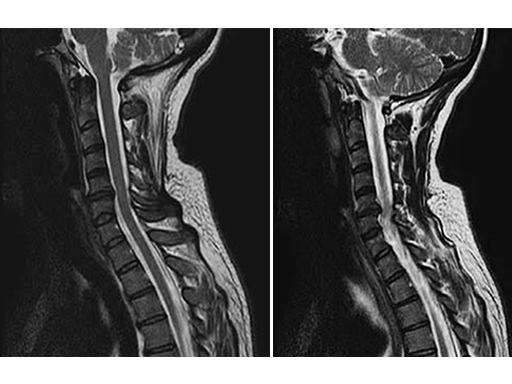

After an uneventful surgical procedure (Fig. 2) and recovery, the preoperative pain syndrome resolved completely.